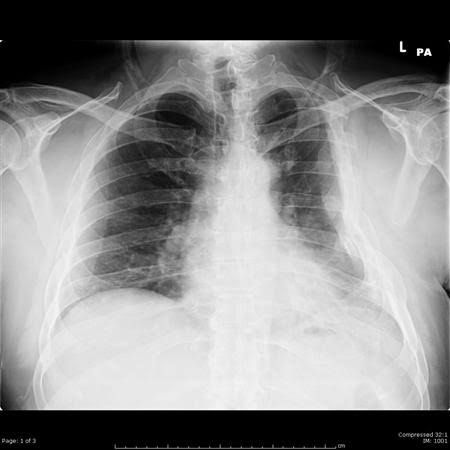

The primary cause of a flail chest is blunt thoracic trauma, or chest trauma, which is an injury caused by a forceful impact with a dull object or surface. Blunt traumas can occur by falls, abuse, car crashes, or as a result of pressure on the sternum and chest during cardiopulmonary respiration (CPR).